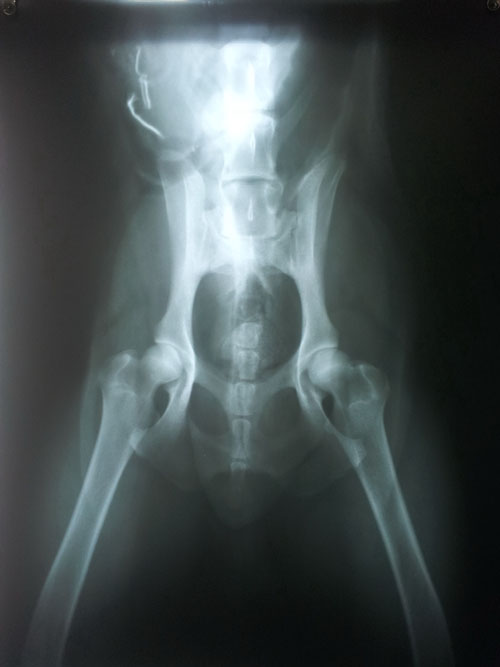

HD - Normal